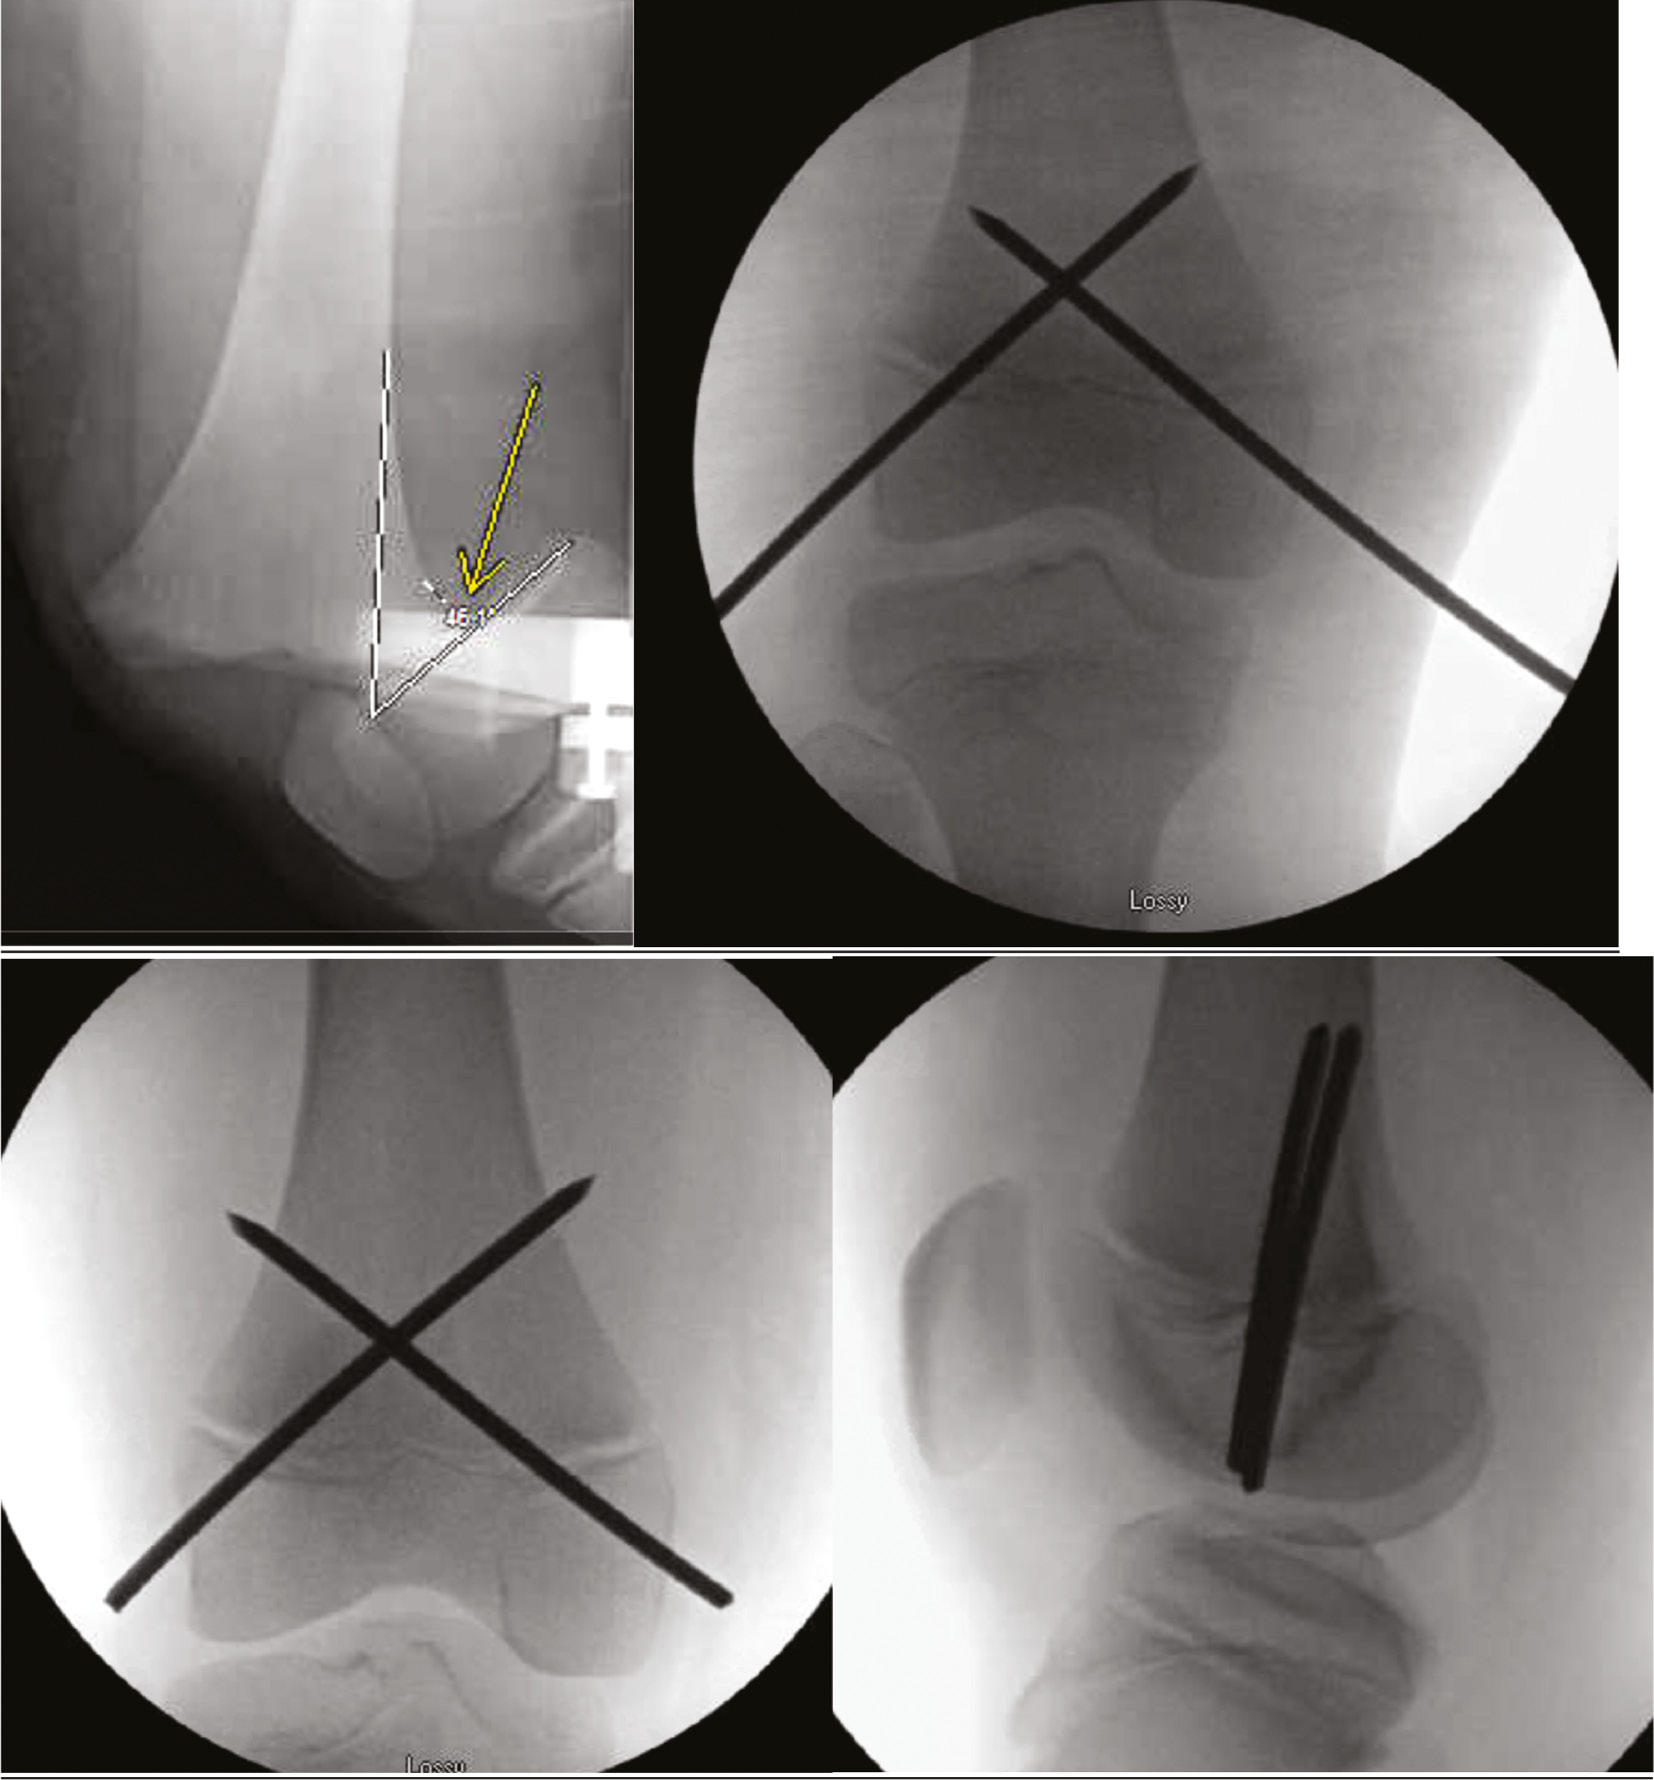

Closed reduction and percutaneous pin fixation can occur in either the supine or the prone position.60 Percutaneous fixation construct consists of two, crossed, transphyseal 3.2-4.5 mm Steinmann pins which may be placed antegrade or retrograde (Figure 15).

Figure 15. A 9-year-old football player sustained a Salter-Harris 1 distal femur fracture. Closed reduction and crossed pin fixation were performed. The pins were likely placed through the joint capsule; thus, to avoid pin tract infection that could lead to septic arthritis, they were cut off below the skin. These pins were removed in the operating room at 5 weeks after injury.